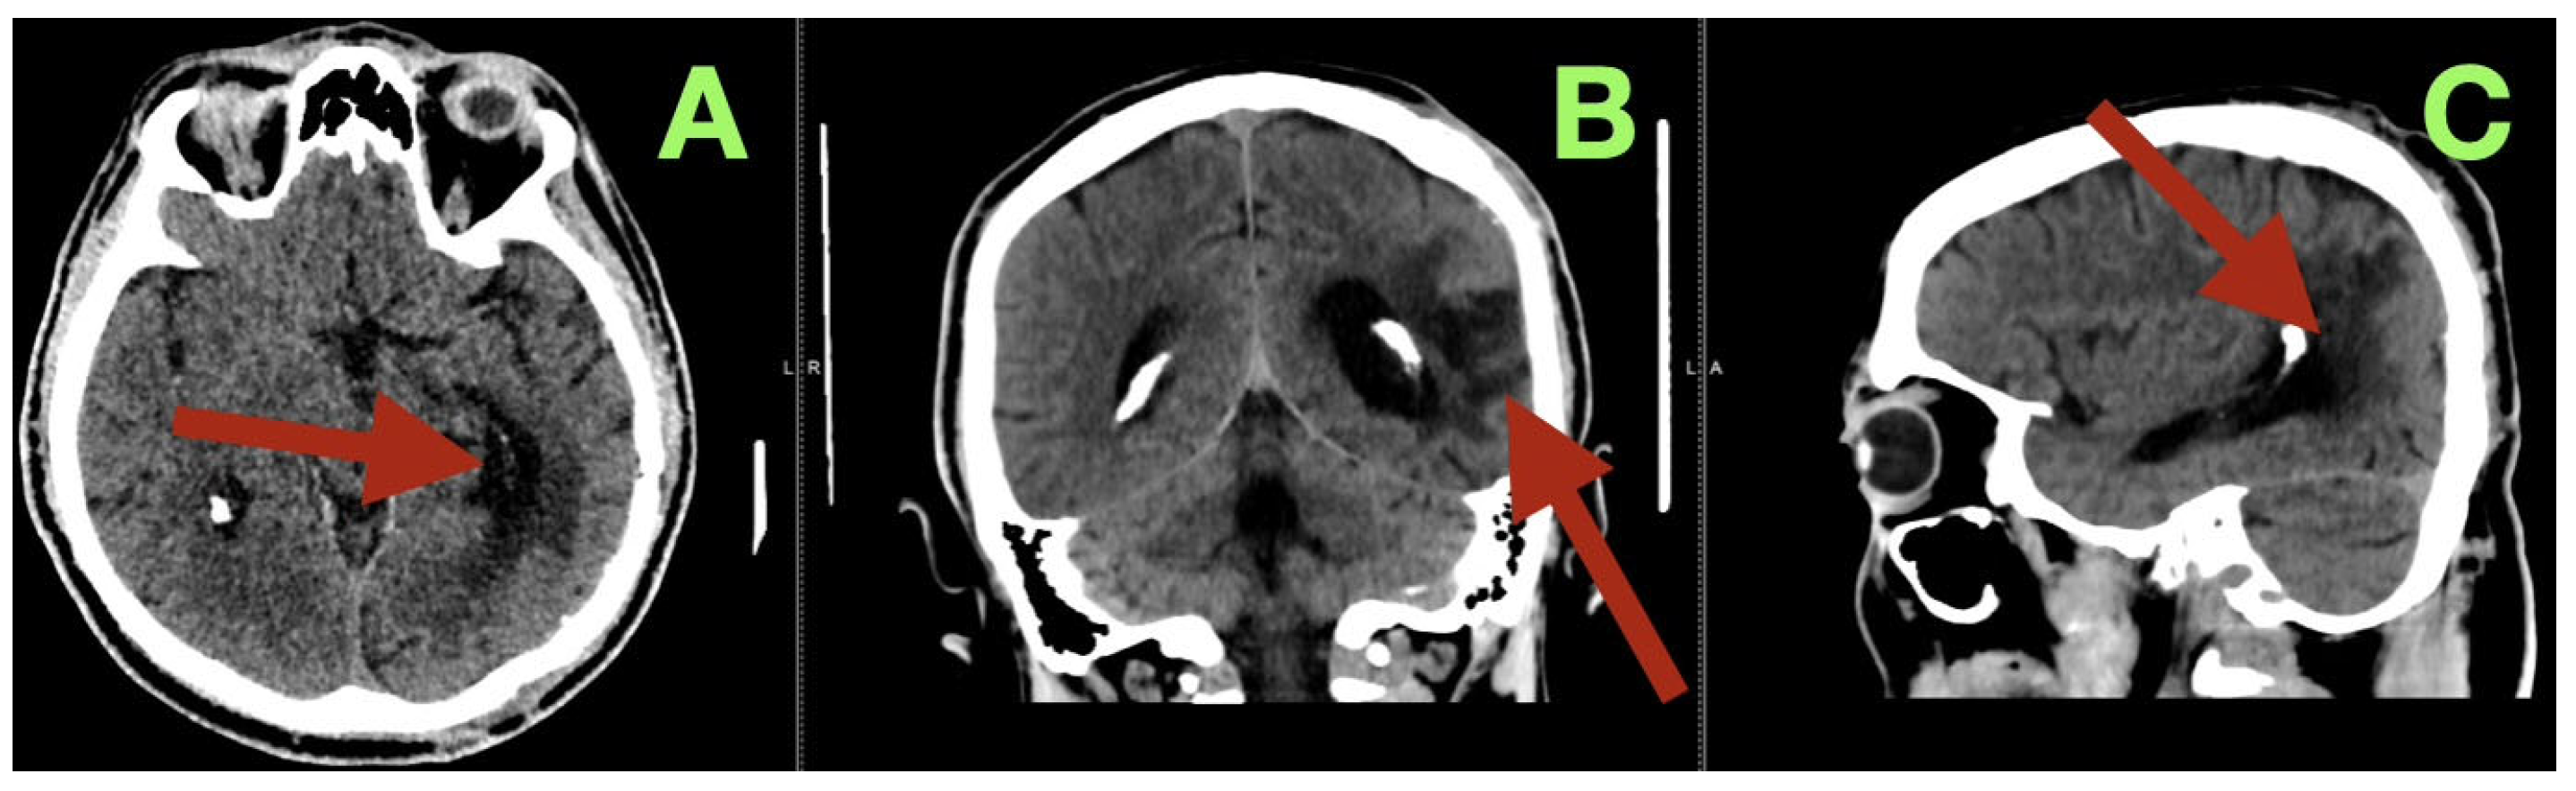

Angiographic studies, particularly selective cerebral angiography, utilizing bilateral internal carotid and left vertebral artery injections established a comprehensive, detailed vascular map of the suspected lesion clinically determined to be an AVM. Selective cerebral angiography established the presence of a compact, high-flow left temporo-parieto-occipital AVM of approximate dimensions 40 × 30 mm in size. The AVM nidus was located deep to the confluence of the posterior superior temporal, angular, and lateral occipital gyri, which is an anatomically unique location representing the crossroads of the posterior perisylvian cortex, visual association areas, and posterior inferior parietal lobule (Figure 1A–D).

The AVM was found to receive blood supply from four different vascular territories: distal posterior cerebral artery (P4) branches from the calcarine and lingual cortices, distal middle cerebral artery (M4) branches from the temporal lobe, a branch from the anterior cerebral artery (A4) from the medial surface of the hemisphere, and a small twig from the superior cerebellar artery ascending along the tentorial edge (Figure 1A–D and Figure 2A,B). These multiple and diverse arteries converge and create a complex multi-directional shunt that supports high velocity flow and maintains parenchymal perfusion through inter-territorial anastomoses. The MCA feeders penetrate the posterior Sylvian fissure, which correlates with the patient’s expressive language hesitancy and phonemic errors. The PCA branches course through the temporal horn roof, which correlates with the patient’s right inferior quadrantanopia. The ACA feeds the superior aspect of the nidus bordering the paracentral lobule and correlates with the mild contralateral pyramidal hyperreflexia.

The AVM drains through two main channels creating a dual-drainage system. A superficial cortical collector ascends obliquely to the superior sagittal sinus via the vein of Trolard. An additional channel of venous outflow is an inferior-lateral trunk that ascends to the transverse-sigmoid junction via a dilated vein of Labbe (Figure 1C,D). Both veins are ectatic but smooth walled and simultaneous opacification confirms high flow and low resistance shunting with no evidence of thrombosis or segmental stenosis. There were no intranidal aneurysms, venous varices or aneurysmal dilatations of the feeding arteries.

Figure 1. Preoperative digital subtraction angiography (DSA). (A): Lateral projection during selective left internal carotid injection demonstrates a compact, high-flow nidus (arrow) centered at the temporo-parieto-occipital junction. The arterial convergence from distal MCA and PCA branches is clearly visualized, with early venous filling consistent with a high shunt volume. (B): Anteroposterior projection highlights the dense arteriovenous network occupying the posterior perisylvian region (arrow). Multiple feeders from M4, P4, and A4 segments converge toward the nidus, producing an intricate lace-like configuration typical of compact high-flow AVMs. (C): Late arterial phase delineates the dual venous drainage (arrow), with a superior cortical outflow ascending to the superior sagittal sinus and a secondary temporobasal collector directed toward the transverse-sigmoid complex. (D): Venous phase confirms synchronous opacification of both drainage routes (arrow), demonstrating the bidirectional flow pattern and the absence of venous outflow restriction. The preserved parenchymal perfusion surrounding the nidus suggests a stable hemodynamic equilibrium between the AVM and eloquent cortical territories.